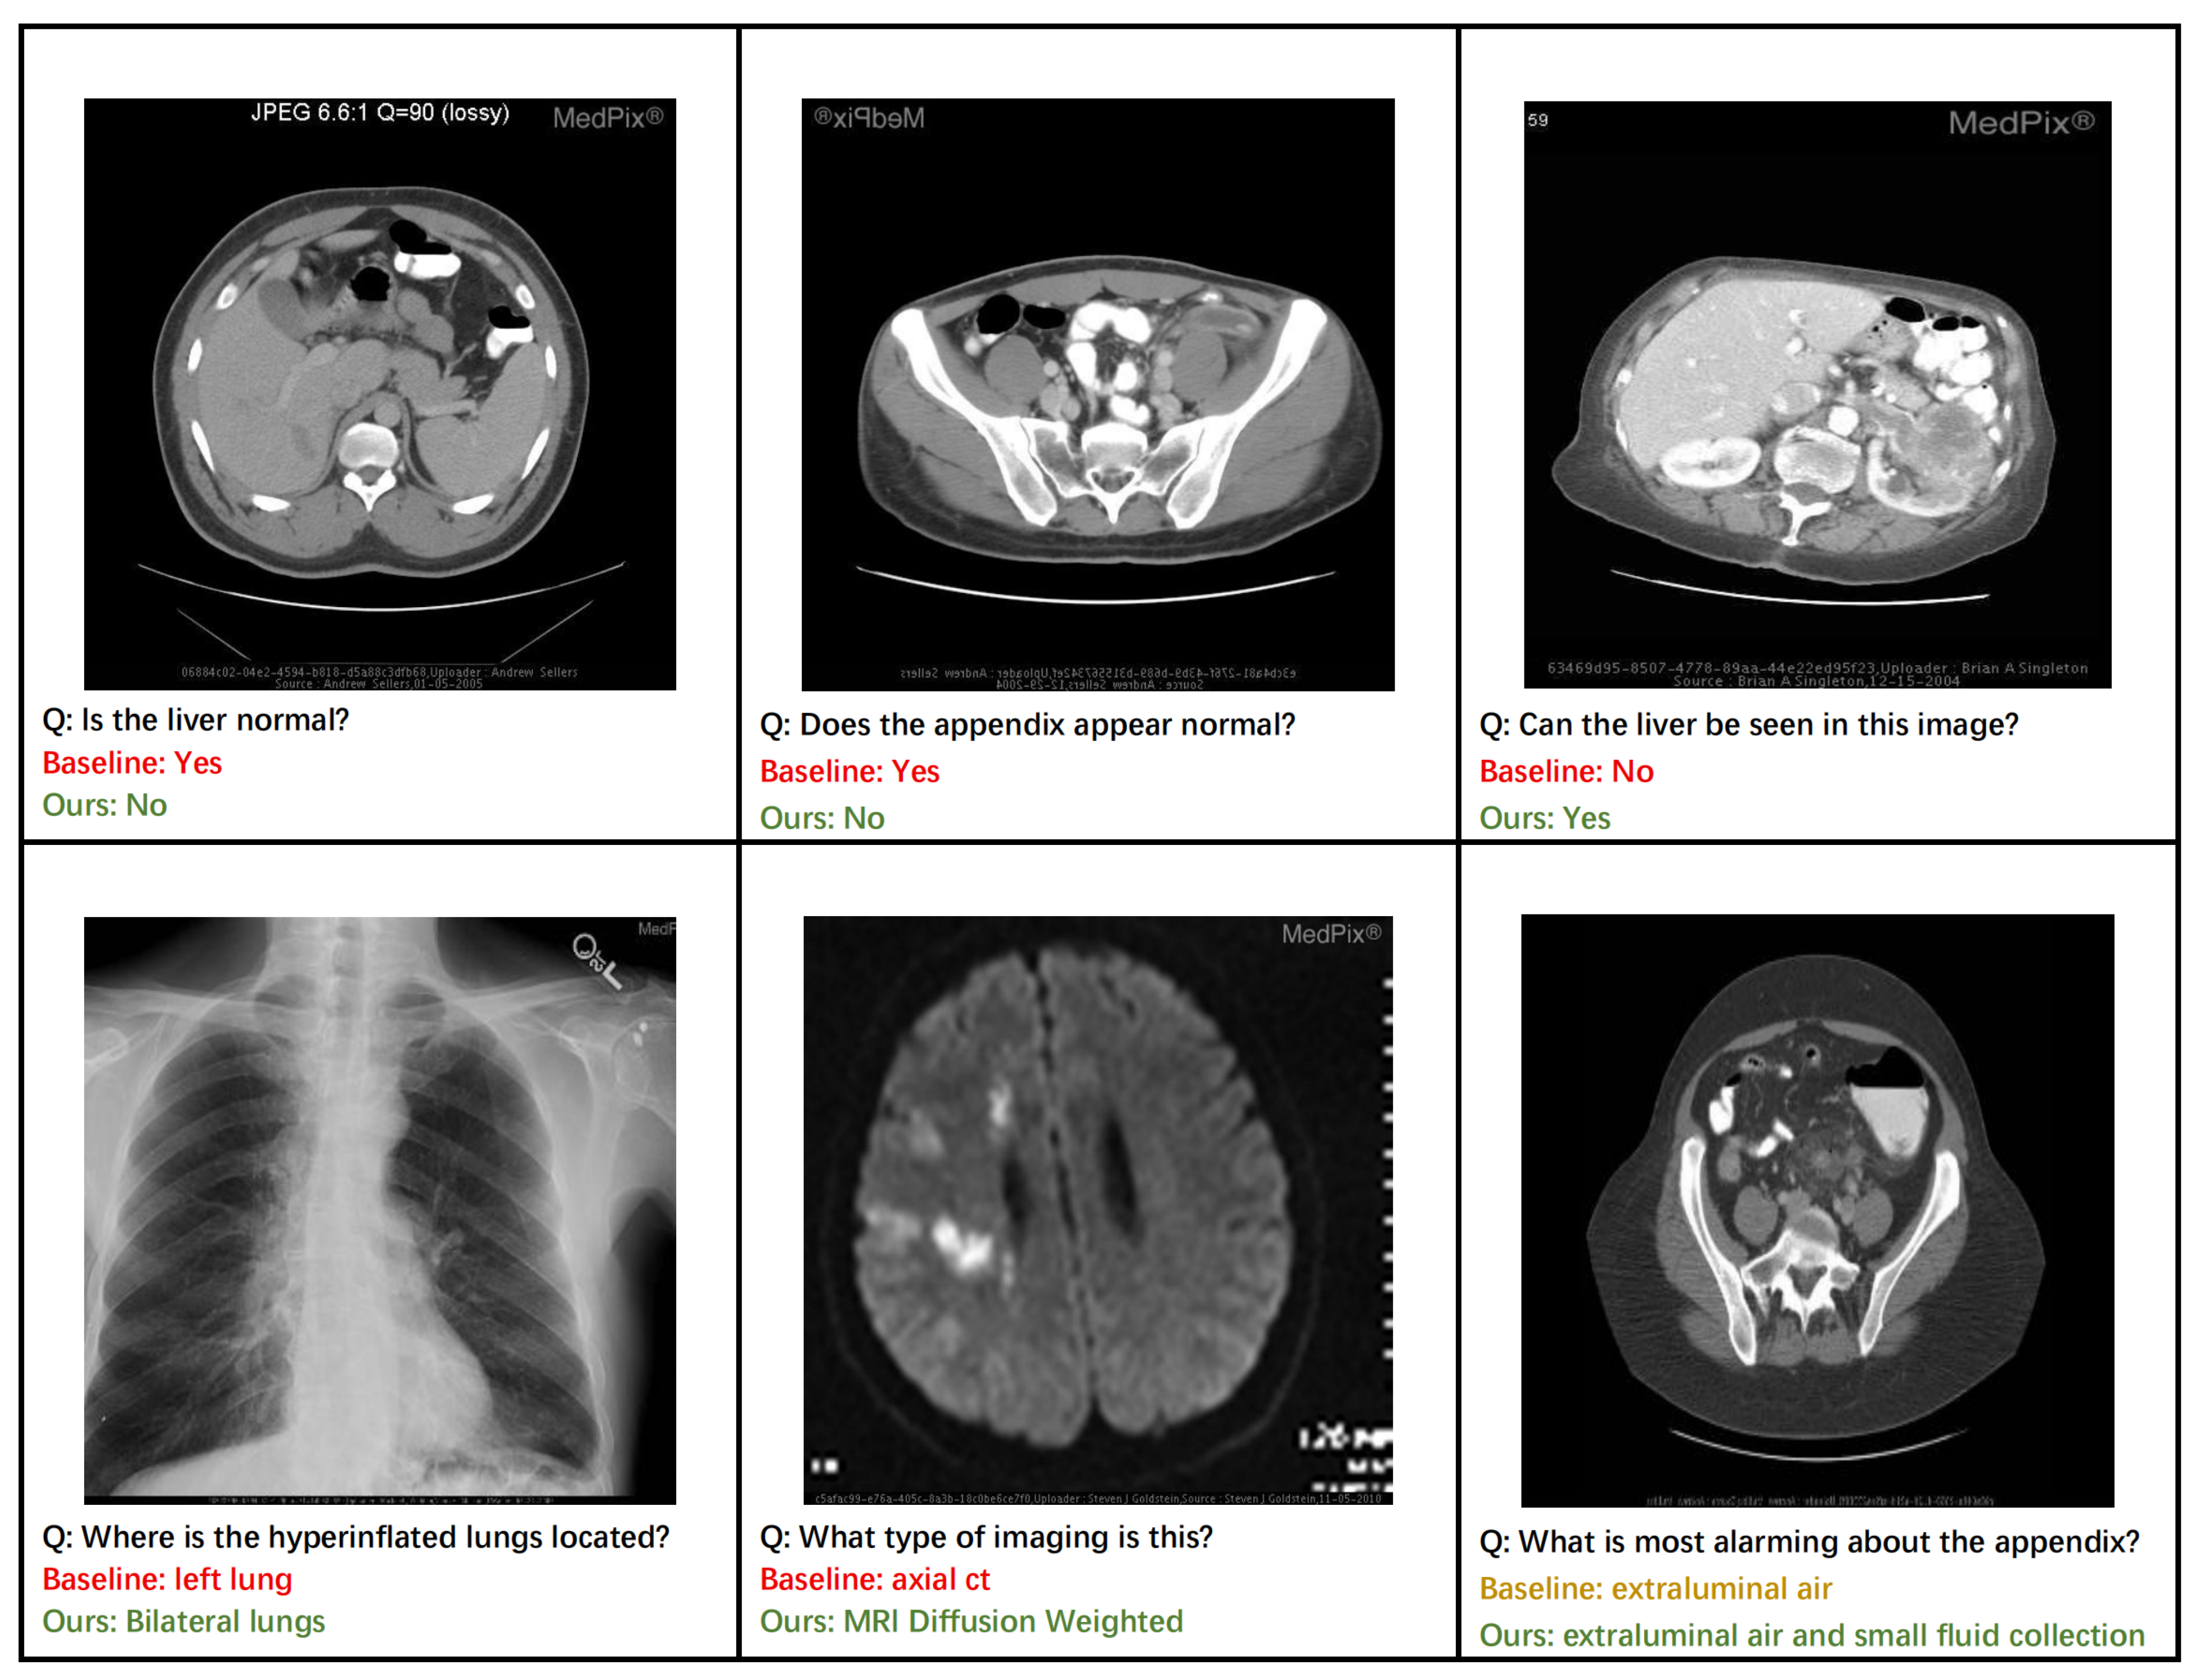

4.7. Qualitative Analysis

Figure 6 provides a qualitative analysis that highlights the practical advantages of our ECSA framework. Our model demonstrates superior diagnostic accuracy, correctly identifying abnormalities in the liver and appendix, where a baseline approach might fail (top row). This enhanced discriminative capability is a direct result of the Clinical-Semantic Disambiguation Module (CSDM). By employing a debiased hard negative mining strategy, CSDM learns highly robust representations that can distinguish subtle pathological markers from normal tissue, which is crucial for accurate initial assessments.

Furthermore, the ECSA exhibits a capacity for more comprehensive and clinically nuanced reasoning. For instance, it correctly identifies pathology as affecting ‘bilateral lungs’ rather than a single lung (bottom row, left) and provides a more complete description of findings related to the appendix, noting both ‘extraluminal air and small fluid collection’ (bottom row, right). This ability to generate detailed and complete answers stems from the rich context-aware features produced by CSDM’s cross-modal attention mechanism. The model’s proficiency in knowledge-intensive tasks is also evident, as it correctly identifies the specific imaging modality as ‘MRI Diffusion Weighted’ (bottom row, middle). This level of specificity is enabled by the Prompt-based Knowledge Consolidation Module (PKC), which functions as a retrieval-augmented knowledge base to supply relevant factual information, grounding the model’s response in a vast repository of clinical examples. Together, these cases illustrate how ECSA’s components synergistically contribute to generating responses that are not only more accurate but also more clinically precise and reliable.